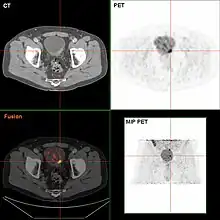

If invasive or high grade (includes carcinoma in situ) cancer is detected on TURBT, an MRI and/or CT scan of the abdomen and pelvis or urogram and CT chest should be conducted for disease staging and to look for cancer spread (metastasis).[56] Increase in alkaline phosphatase levels without evidence of liver disease should be evaluated for bone metastasis by a bone scan.[57] Although 18F-fluorodeoxyglucose (FDG)-positron emission tomography (PET)/CT has been explored as a viable method for staging, there is no consensus to support its role in routine clinical evaluations.[54]